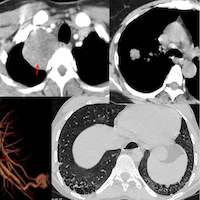

39-yrs old with a 30-yrs old history of asthma on treatment presented with acute exacerbation and a CT scan was done. The only positive finding was multiple lower lobe segments showing mucoid impaction/mucus plugs.

The video is about a recent paper on mucoid impaction in the last 2 cm of the lungs and then down a rabbit hole of mucus scores starting from a seminal 2018 paper to current literature and finally whether it is important or not to mention mucus plugs in the CT chest report in asthmatics.